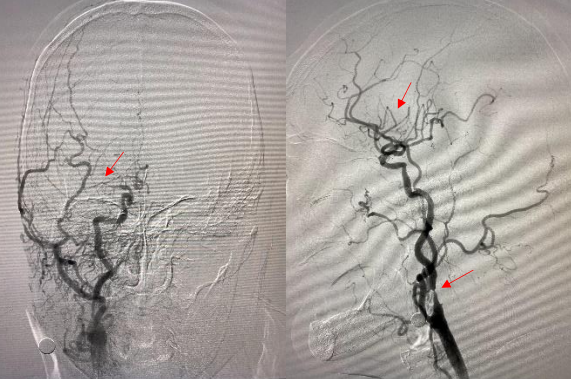

术中因双侧股动脉穿刺均困难,手推造影提示双侧股动脉闭塞。

遂果断另辟蹊径,经肱动脉穿刺成功,行腹主动脉造影证实右侧髂总动脉闭塞,左侧髂总动脉极重度狭窄并串珠样改变,故经股动脉入路此路不通。

头颈部血管造影提示:患者为右侧颈内动脉极重度狭窄合并右侧大脑中动脉闭塞。

由远及近,优先开通右侧大脑中动脉恢复颅内血流,再行右侧颈内动脉起始部支架植入血管成形,顺利开通闭塞血管,颅内血流恢复。